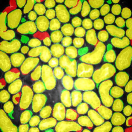

Figure 4 provides an alternative way to show the segmentation results. In particular, yellow regions correspond to true positives which are pixel locations that are identified as tubules in both the groundtruth and segmentation results. Green regions correspond to false positives which are pixel locations that are identified as background in groundtruth but tubules in segmentation results. Similarly, red pixels correspond to false negatives, namely pixel locations identified as tubules in the groundtruth but background in segmentation results, and black pixel regions correspond to true negative that are identified as background in both groundtruth and segmentation results. The green regions indicate Type-I error (false alarm) regions and the red regions represent Type-II error (miss) regions. As observed from Figure 4, the segmentation results in the first row contained large red regions which mean large regions of tubules were missed. Conversely, the segmentation results shown in the second row contained many green regions indicating many background regions were falsely segmented as tubule regions. In contrast, the segmentation results in the third row had reasonably small green regions and red regions which indicate that the deep learning based segmentation results had higher pixel accuracy with relatively low Type-I and Type-II errors.

where , , , and are defined to be the number of segmented pixels that were labeled as true positives, true negatives, false positives, false negatives, respectively. denotes the total number of pixels in a image. These three pixel-based metrics obtained for different segmentation results are provided in Table 1. As shown in Figure 4, Type-II errors of the first three methods (3Dac, 3DacIC, 3Dsquassh) were much higher compared to other methods. Similarly, Type-I errors of next three methods (Ellipse Fitting, Jelly Filling, Steerable Filter) were much higher than those of the other methods. However, 2DCNN and 2DCNNIC had high PA and relatively low Type-I and Type-II errors.